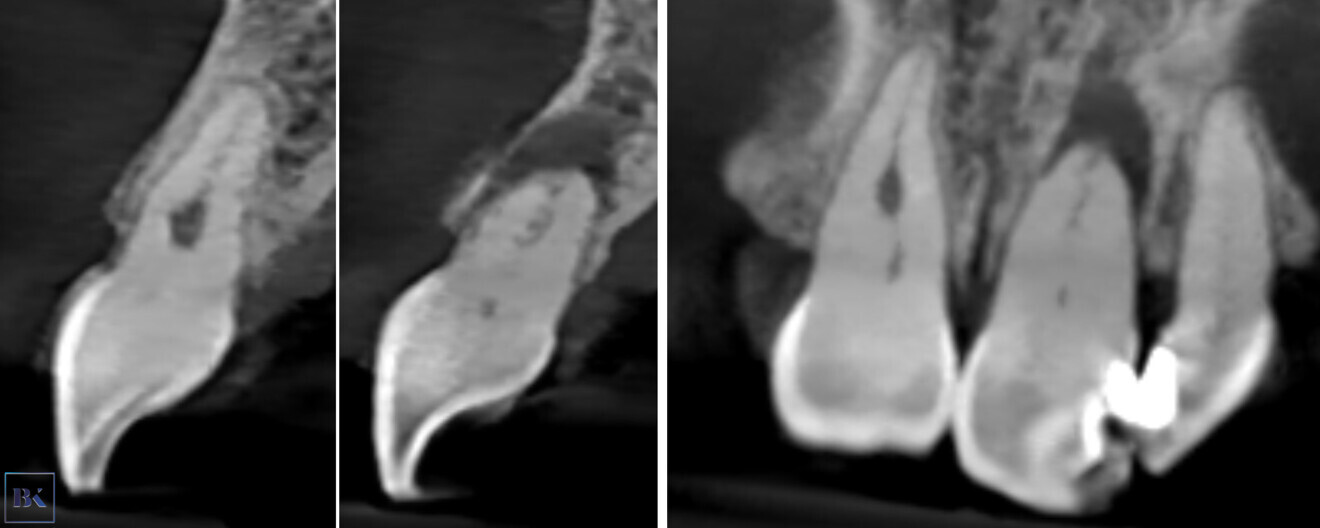

The access cavity was performed with the EndoGuide bur with the aid of the software. After reaching the depth of drilling on the prepared guide, another CBCT scan was performed to check the accuracy of the access cavity (Fig. 18). The CBCT scan revealed that the angulation of the access cavity was suitable but that the depth was insufficient. The EndoGuide drill and Navident were used one more time to reshape the access cavity. After gaining patency in the canal, the #10 K-file was used to establish the working length. The canal in the right incisor was shaped with Endostar E3 Azure up to size 40/0.04, and the canal in the left incisor was shaped up to size 45/0.04. In both canals, the irrigation protocol was performed with 5.25% sodium hypochlorite and 40.0% citric acid. Both solutions were activated with Eddy sonic tips, and sodium hypochlorite was additionally activated with Elements Free for intra-canal heating. The canals were dried with paper points (Fig. 19) and obturated with warm gutta-percha using the continuous wave technique, and a control radiograph was performed (Fig. 20). Finally, the composite sealing was performed and the occlusal check was done (Fig. 21).

Figs. 18a & b: CBCT check, sagittal plane. The axis of the access cavity was visible for both teeth.